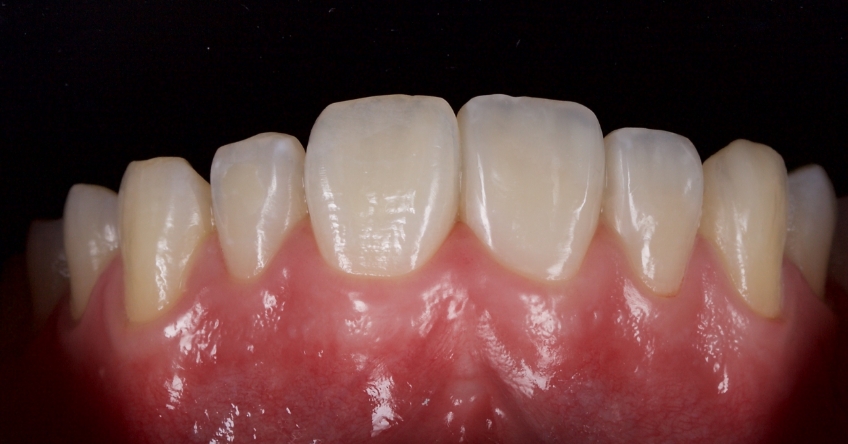

This 21-year-old male presented with an uncomplicated enamel-dentin fracture of the upper right central, lateral incisor, and canine following a fall.